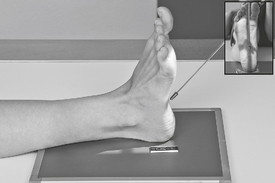

• Extend (plantar flex) foot by sliding foot and IR distally while keeping plantar surface flat on IR. (Support with sandbags to keep foot and IR from sliding farther.)